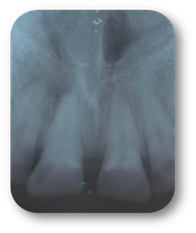

A la exploración física refirió dolor a la percusión y palpación en la pieza 2.1, radiográficamente se observó fractura horizontal en el tercio medio de la raíz (Fig.1), por lo que se decidió ferulizar de la pieza 1.2 a 2.2 (Fig.2).

Fig. 1

Fig. 2